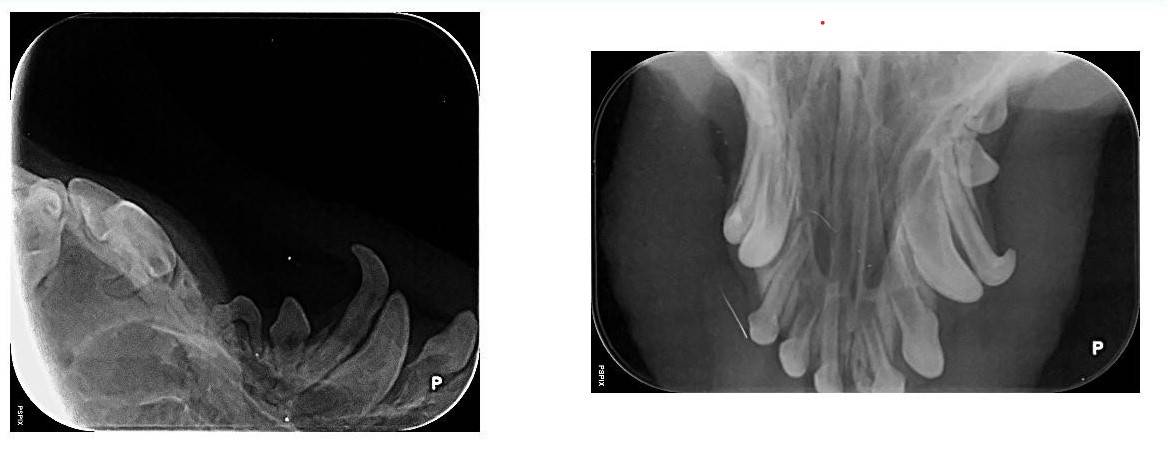

Nouveau : Radiologie dentaire chien ou chat

La clinique Vétérinaire est équipée d'un appareil de radiologie dentaire XMind accompagné d'un systême de développement numérique.

Cet équipement est indispensable à la réalisation d'un bilan dentaire complet sur un chien ou un chat. En effet, la majorité des lésions dentaires chez les carnivores se trouvent sous la gencive et ne se voient pas à l'oeil nu, en particulier les résorptions dentaires chez le chat C'est pourquoi nous conseillons un bilan dentaire lors d'une intervention buccale ou un détartrage de convenance.

toute radiologie dentaire ne peut être effectuée que sous sédation profonde afin que le cliché puisse être effectuée et afin d'obtenir une bonne qualité d'image.

Celà permet de dépister des dents fracturées, abîmées, infectées, les lyses osseuses de la mâchoire. Une infection dentaire latente peut être responsable de complications rénales cardiaques ou hépatiques